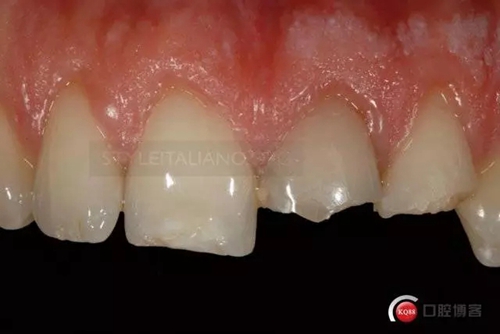

Until the immediate final outcome

242607.jpg